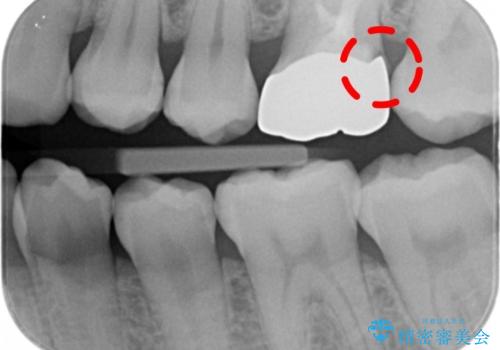

- 検査の結果被せ物の不適合が見つかった患者様です。

被せ物を除去し、根管治療を進めた後に新しい被せ物を装着していきます。

本来は歯茎をしっかりと下げる外科処置が適応となるケースでしたが、ご希望がなかったため最小限の侵襲に抑えて治療を行いました。